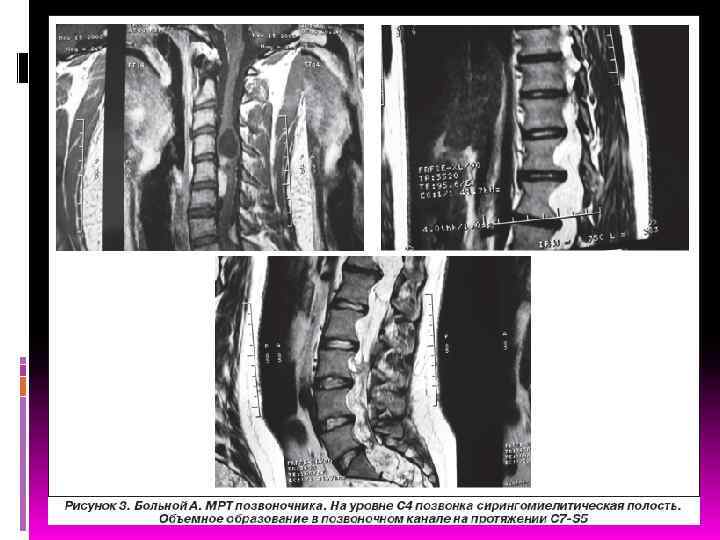

ДИАГНОСТИКА Первичная диагностика NF должна осуществляться педиатрами, подростковыми врачами, участковыми врачами общей практики (семейными врачами), а также узкими специалистами (неврологами, дерматологами, офтальмологами, хирургами, стоматологами) в процессе динамического диспансерного обслуживания населения. Важно помнить, что процесс развития клинической симптоматики NF является динамическим, поэтому важны преемственность между специалистами различного профиля и своевременное проведение комплекса дополнительных методов диагностики, включая КТ/МРТ головного и спинного мозга.